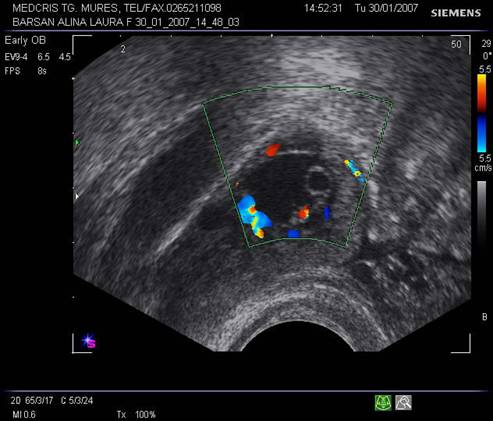

Fig nr 57 La exam. Doppler color, formatiunea retrouterina, cu ecou hipoecogen central, are o buna vascularizatie ( aceeasi sarcina tubara pavilionara ca in fig. precedenta )

![]()

Fig nr58

Sac ovular intratubar ampular ( dg. complet doar laparoscopic, aici cu sageata ) cu imagine

caracteristica de coroana trofoblastica bine vascularizata la exam doppler

color . Alaturi se remarca ovarul drept cu corp galben, tot cu ecou hipoecogen

central ( marcat cu doua sageti )

Fig nr 59 Aceeasi sarcina ca in figura precedenta, in sacul ovular marcat cu o linie, se distinge clar sacul lui Yolk, alaturi de corpul galben ovarian drept